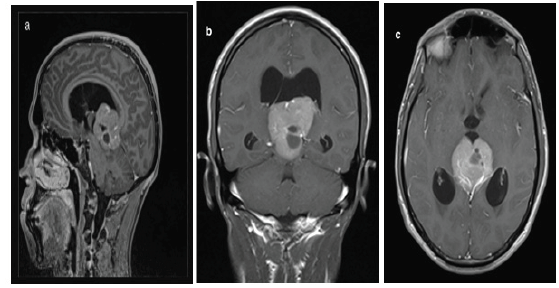

Figure 1a, b, c:MRI T1-weighted postcontrast views: tumorous expansion of solid-cystic nature in the pineal region (arrows), penetrating the 3rd ventricle with compressed aqueduct of Silvius and 3-ventricular hydrocephalus.

We report the case of a 23-years-old male with an unremarkable past medical history who was admitted in the department of medical oncology at Hassan II University Hospital for headache rebellious to symptomatic treatment; associated to diplopia. Neurological examination did not reveal any neurological deficit. Cerebral Computed tomography (CT) scan showed an expansive process of the pineal area measuring 35.5*44*52.5mm with double component containing calcifications. A subsequent gadolinium-enhanced magnetic resonance imaging (MRI) revealed a bulky expansive process of the pineal area, isointense T2 and T1 compared to gray substance (Figure 1a-1c ). The lesion measured 4*4*4.6cm and caused considerable masse effect and biventricular hydrocephalus. These neuroradiological features evoked a germinoma of the pineal area. Tumor markers were assessed at the moment of diagnosis and showed a normal value of alpha-fetoprotein (AFP) and a slightly high level of beta-human chorionic gonadotropin (b-HCG) at 7.87 IU/L (n=0-5 IU/L). A lumbar puncture was performed, and the cytology of the cerebrospinal fluid confirmed the diagnosis of the germinoma (Figure 2a). Patient underwent a medullar MRI and thoracic scan that did not show metastases (Figure 2b).